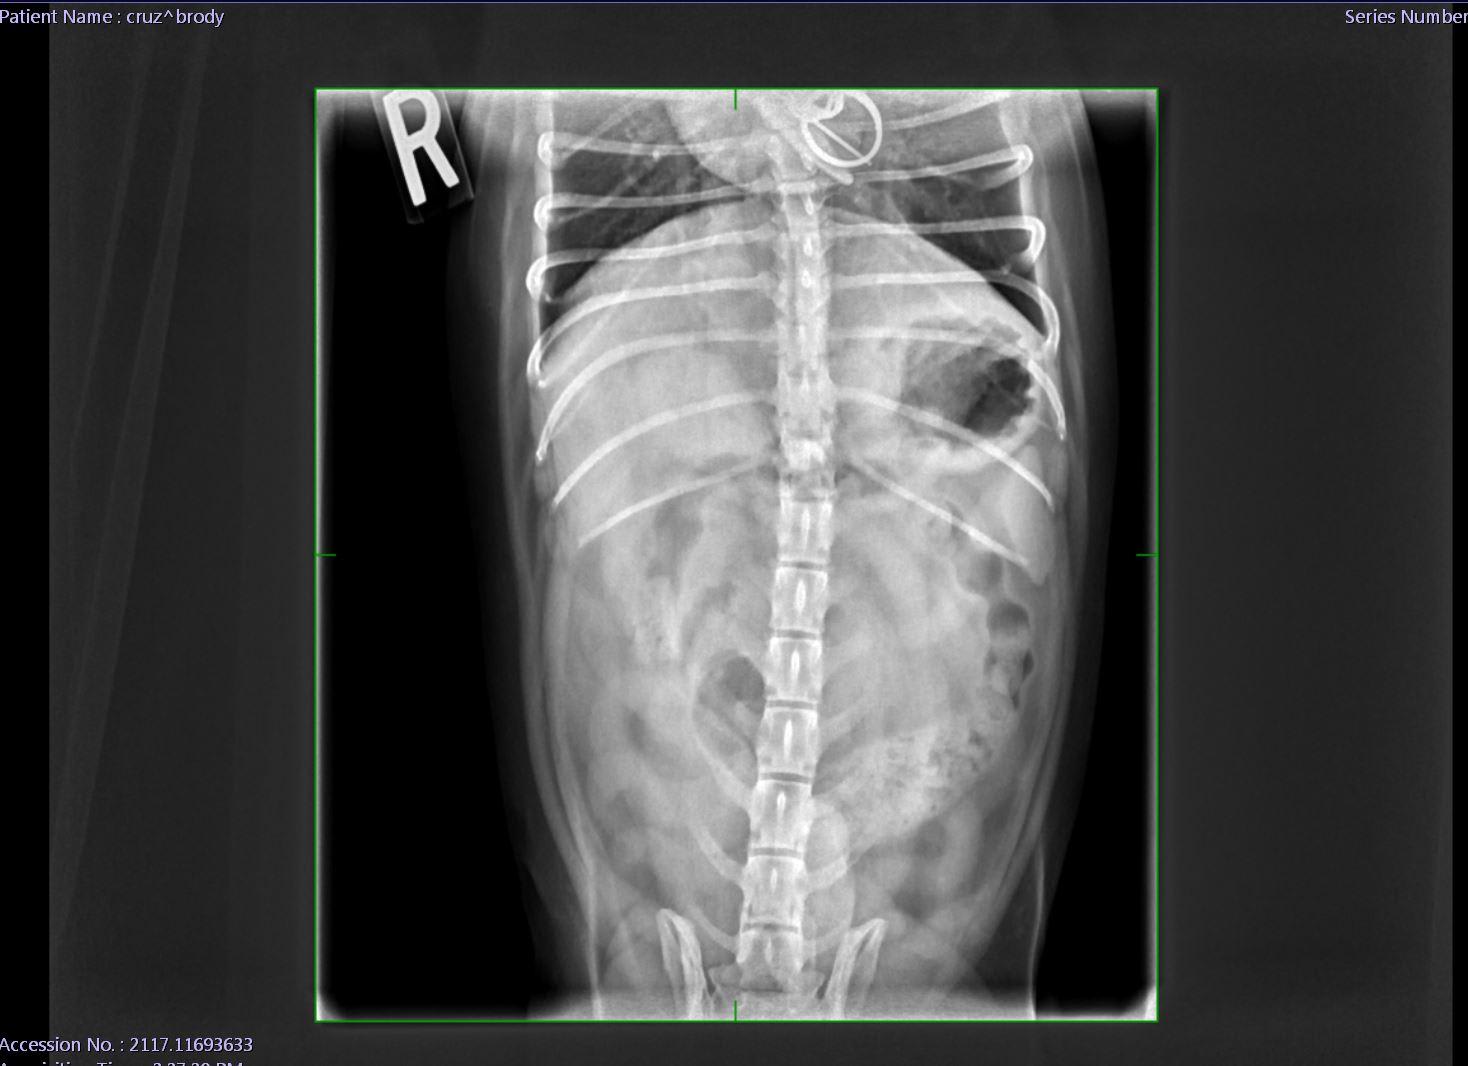

my dog Swallowed a small piece of wrapper from a salami that has a small metal piece attached on 12/18. He started throwing up yellow bile for about four days I took him in on Saturday for x-rays which showed the object still in his stomach. He has been acting normal, he eats, drinks water he goes on walks and pees/poops fine but the object has not moved from the stomach after I took him to the vet once again this Monday, 12/24. Vet recommended to wait till Jan 2 but I’m afraid that’s too long.